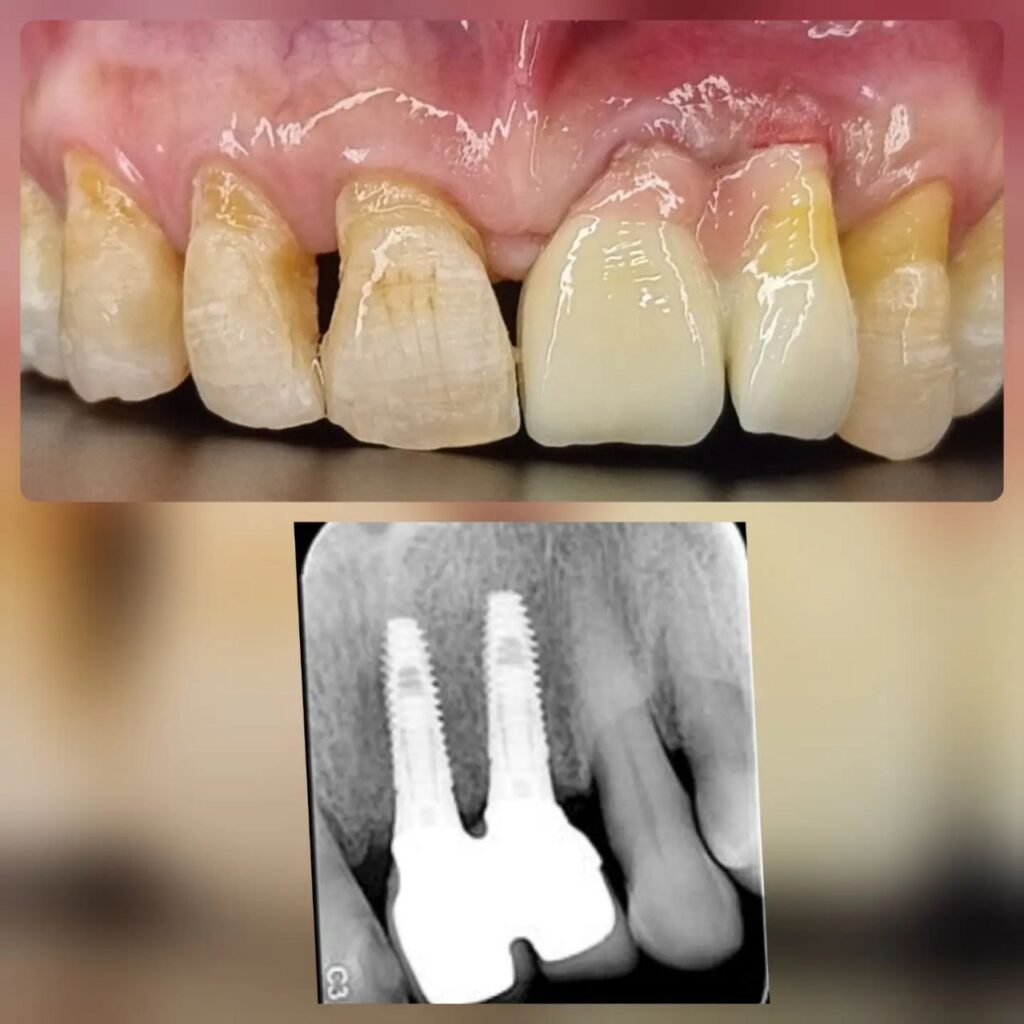

کاشت ایمپلنت دندان

اطمینان حاصل کردن از اینکه دندانهایتان به نحوی زیبا و طبیعی جایگزین شدهاند، از اهمیت بسیاری برخوردار است. ایمپلنت دندان به عنوان یک روش درمانی دائمی در دندانپزشکی شناخته میشود که حاصل آن، یک دندان زیبا و طبیعی در دهان شما خواهد بود.

هرچند که این روش درمانی هزینهی بیشتری نسبت به روشهای دیگر دارد، اما ارزش زیبایی که ایجاد میکند، قابل انکار نیست. ایمپلنتها به قدری شبیه به دندانهای طبیعی هستند که به سختی میتوان آنها را از دیگر دندانها تشخیص داد.